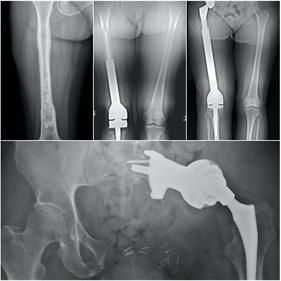

El 80% de las metástasis óseas se relacionan, por orden de frecuencia con el cáncer de mama, pulmón, próstata y riñón. Las metástasis óseas que se localizan en huesos largos suelen localizarse en el fémur, con especial predilección por la zona de la cadera.

El fémur es la localización principal, con predominio de la zona de la cadera. Otras localizaciones son la columna vertebral, la pelvis, los huesos planos y el húmero. En la espalda el dolor suele estar presente antes que los cambios radiográficos, mientras que cuando el dolor se localiza en los huesos largos suelen ya existir lesiones con riesgo de fractura.

En el cáncer diseminado el tratamiento de las metástasis suele ser paliativo, mediante estabilización de la fractura con osteosíntesis o implante de prótesis. En ocasiones la osteosíntesis se suplementa con aporte de cementos biológicos para aumentar la estabilidad o se realiza radioterapia complementaria. En casos de metástasis únicas, el tratamiento quirúrgico radical de la metástasis puede estar indicado, lo que hace necesaria la valoración conjunta de traumatología oncológica y oncología médica ante la detección de una lesión metastásica ósea en nuestra práctica.